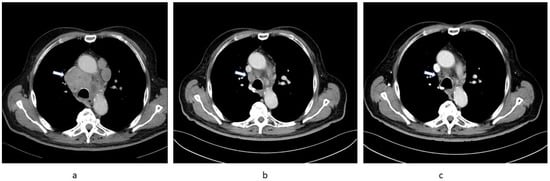

2.1. Patient 1

2.2. Patient 2